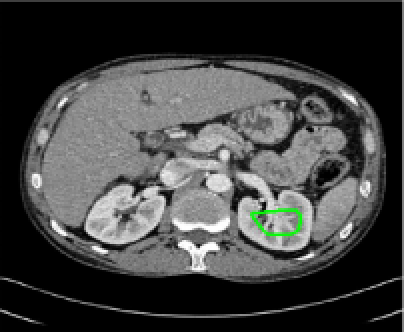

Four sets of test results are shown below. In Test 1 we compare models M1 – M6 to the proposed model M7 for two images which are hard to segment. The first is a CT scan from which we would like to segment the lower portion of the heart, the second is an MRI scan of a knee and we would like to segment the top of the Tibia. See Figure 9 for the test images and the marker sets used in the experiments. In Test 2 we will review the sensitivity of the proposed model to the main parameters. In Test 3 we will give several results achieved by the model using marker and anti-marker sets. In Test 4 we show the initialisation independence and marker independence of the Geodesic Model on real images.

In this test we give the segmentation results for models M1 – M7 for the two challenging test images shown in Figure 9. The marker and anti-marker sets used in the experiments are also shown in this figure. After extensive parameter tuning, the best final segmentation results for each of the models are shown in Figures 10 and 11. For M1 – M4 we obtain incorrect segmentations in both cases. In particular, the results of M2 and M4 are interesting as the former gives poor results for both images, and the latter gives a reasonable result for Test Image 1 and a poor result for Test Image 2. In the case of M2, the regularisation term includes the edge detector and the distance penalty term (see (4)). It is precisely this which permits the poor result in Figures 10(b) and 11(b) as the edge detector is zero along the contour and the fitting terms are satisfied there (both intensity and area constraints) – the distance term is not large enough to counteract the effect of these. In the case of M4, the distance term and edge detector are separated from the regulariser and are used to weight the Chan-Vese fitting terms (see (9)). The poor segmentation in Figure 11(b) is due to the Chan-Vese terms encouraging segmentation of bright objects (in this case), weighting enforces these terms at all edges in the image and near . In experiments, we find that M4 performs well when the object to segment is of approximately the highest or lowest intensity in the image, however when this is not the case, results tend to be poor. We see that, in both cases, models M5 and M6 give much improved results to M2 and M4 (obtained by incorporating the geodesic distance penalty into each). The proposed Geodesic Model M7 gives an accurate segmentation in both cases. It remains to compare M5, M6 and M7. We see that M5 is a non-convex model (and cannot be made convex [39]), therefore results are initialisation dependent. It also requires one more parameter than M6 and M7, and an accurate set to give a reasonable area constraint in (4). These limitations lead us to conclude M6 and M7 are better choices than M5. In the case of M6, it has the same number of parameters as M7 and gives good results. M6 can be viewed as the model M7 with weighted intensity fitting terms (compare (18) and (30)). Experimentally, we find that the same quality of segmentation result can be achieved with both models generally, however M6 is more parameter sensitive than M7. This can be seen in the parameter map in Figure 12 with M7 giving an accurate result for a wider range of parameters than M6. To show the improvement of M7 over previous models, we also give an image in Figure 13 which can be accurately segmented with M7 but the correct result is never achieved with M6 (or M3). Therefore we find that M7 outperforms all other models tested M1 – M6.

Test 3 – Further Results from the Geodesic Model M7. In this test we give some medical segmentation results obtained using the Geodesic Model M7. The results are shown in Figure 14. In the final two columns we use anti-markers to demonstrate how to overcome blurred edges and low contrast edges in an image. These are challenging and it is pleasing to see the correctly segmented results.